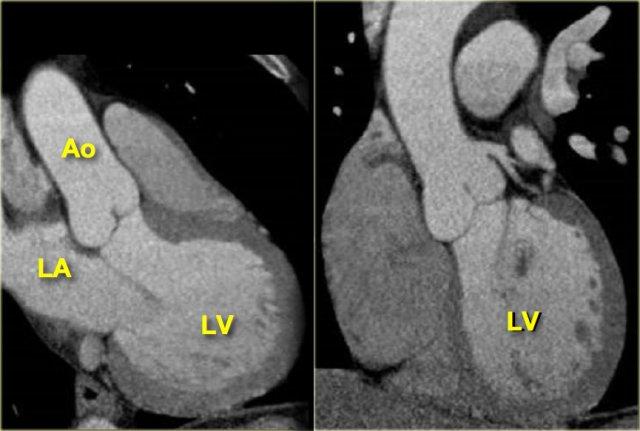

Khi xác định được ranh giới giữa van hai lá và van động mạch chủ trên các lát cắt ngang và xoay hình ảnh từ điểm này, có thể tái tạo mặt cắt 3 buồng như hình ảnh bên trái.

Trên hình ảnh này, nhĩ trái, thất trái, van hai lá, van động mạch chủ và đoạn gần của động mạch chủ lên đều được hiển thị.